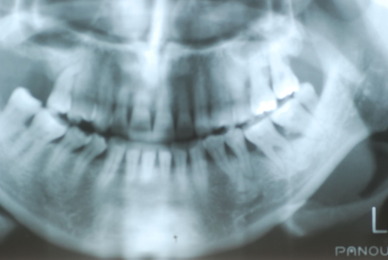

![894_965331056876880_8443672701507457881_n[1]](https://livedoor.blogimg.jp/netdental/imgs/f/6/f6b74161-s.jpg)